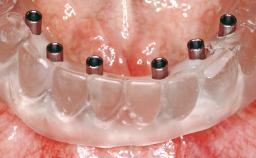

# of Implants 2

Type of Implants One-Piece

Loading Protocol Immediate (bar only)